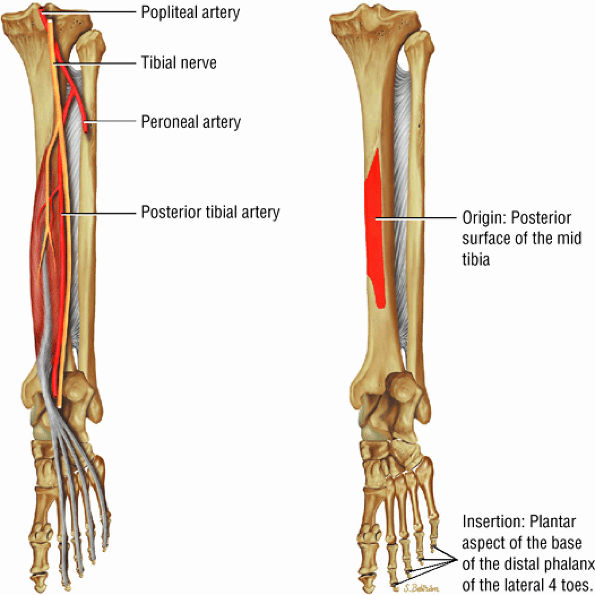

The deep group of posterior leg muscles comprises the popliteus (see discussion in Chapter 4 on the knee), the flexor hallucis longus (Fig. 5.9), the flexor digitorum longus (Fig. 5.10), and the tibialis posterior (Fig. 5.11).

FIGURE 5.10 ● FLEXOR DIGITORUM LONGUS The flexor digitorum longus (FDL) flexes the phalanges of the lateral four toes and plantarflexes the foot. The FDL is superficial to the flexor hallucis in the sole of the foot. Paratenonitis of the FDL is more infrequent than involvement of the flexor hallucis longus.

FIGURE 5.11 ● TIBIALIS POSTERIOR The tibialis posterior plantarflexes and inverts the foot. The tibialis posterior tendon passes over (superficial to) the deltoid and changes from a tubular tendon to a flattened structure containing a fibrocartilaginous sesamoid (under the plantar calcaneonavicular ligament).